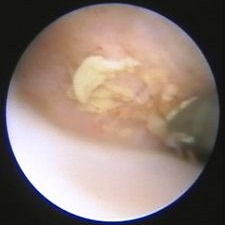

Biopsie pro histologické posouzení

Ze suspektních míst odebíráme cíleně vzorek (biopsii) k histologickému posouzení. Výkon zpravidla netrvá déle než 3-5 minut. Bioptické kleště jsou patrné v pravém rohu snímku.

• Datum: Leden 2014

• Druh: Biopsie

• Lékař: MUDr. Petr Kovář